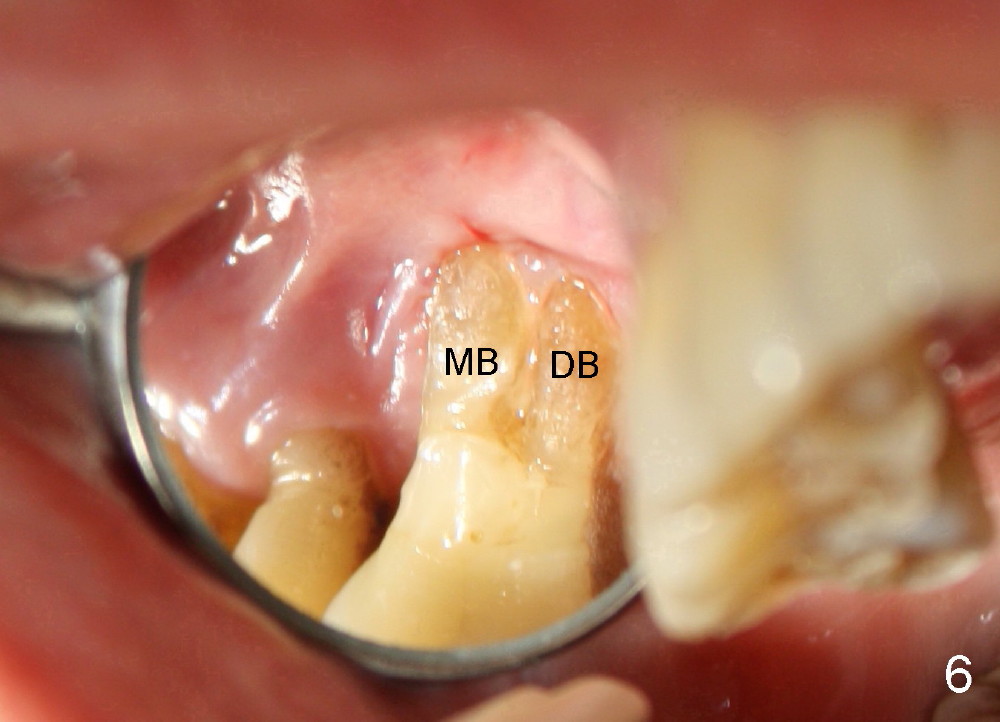

One year later, a 68-year-old lady requests treatment for the same tooth with almost identical conditions (Fig.4-6). Immediate implant is placed with immediate outcome. The difference between these cases is experience and practice.